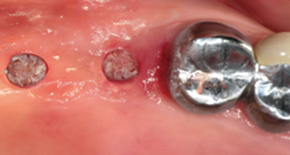

1. Preoperative

2. Body preparation

3. Bone graft

4. Placement of MagiCore